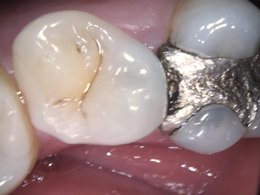

【

口腔内カメラ

】

口腔内カメラの画像